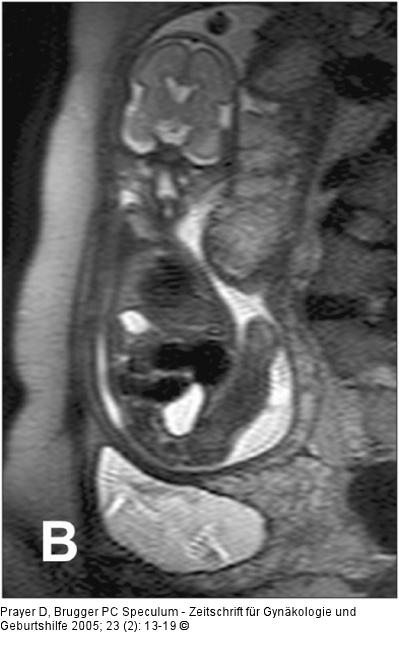

Abbildung 6a-b: Pränatale Magnetresonanztomographie Normale, homogene und glatt begrenzte Plazenta in der 26. SSW. B. gleiche SSW, die Plazenta hat jedoch eine pathologisch unruhige Binnenstruktur und eine unregelmäßige Oberfläche. Der Fetus weist eine Wachstumsrestriktion auf. |

Normale, homogene und glatt begrenzte Plazenta in der 26. SSW. B. gleiche SSW, die Plazenta hat jedoch eine pathologisch unruhige Binnenstruktur und eine unregelmäßige Oberfläche. Der Fetus weist eine Wachstumsrestriktion auf. |